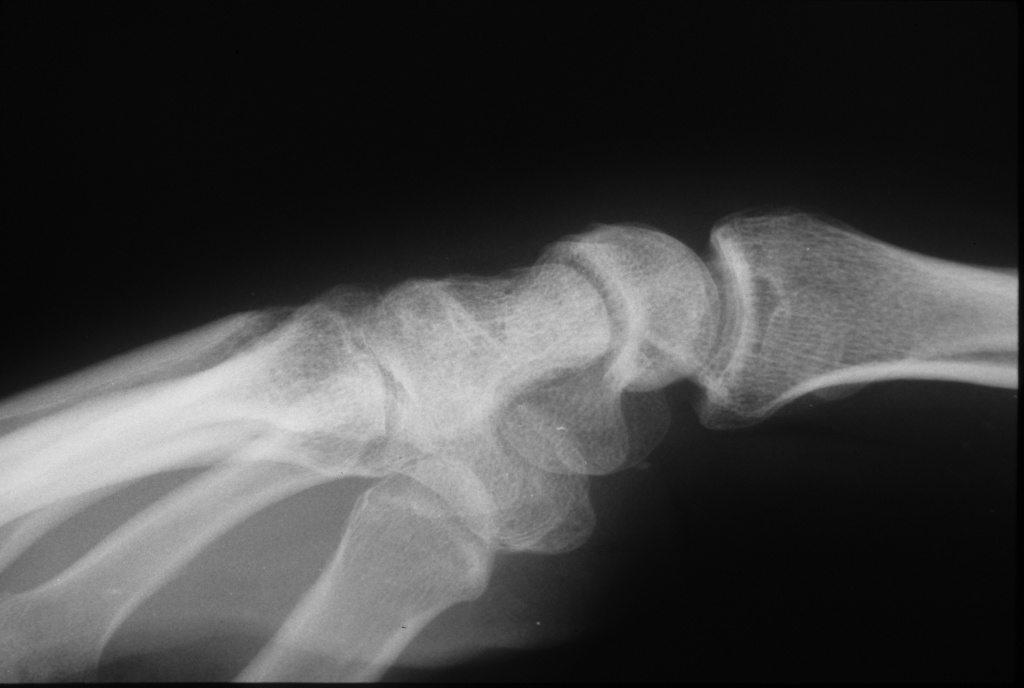

Another patient with "kissing osteophytes"